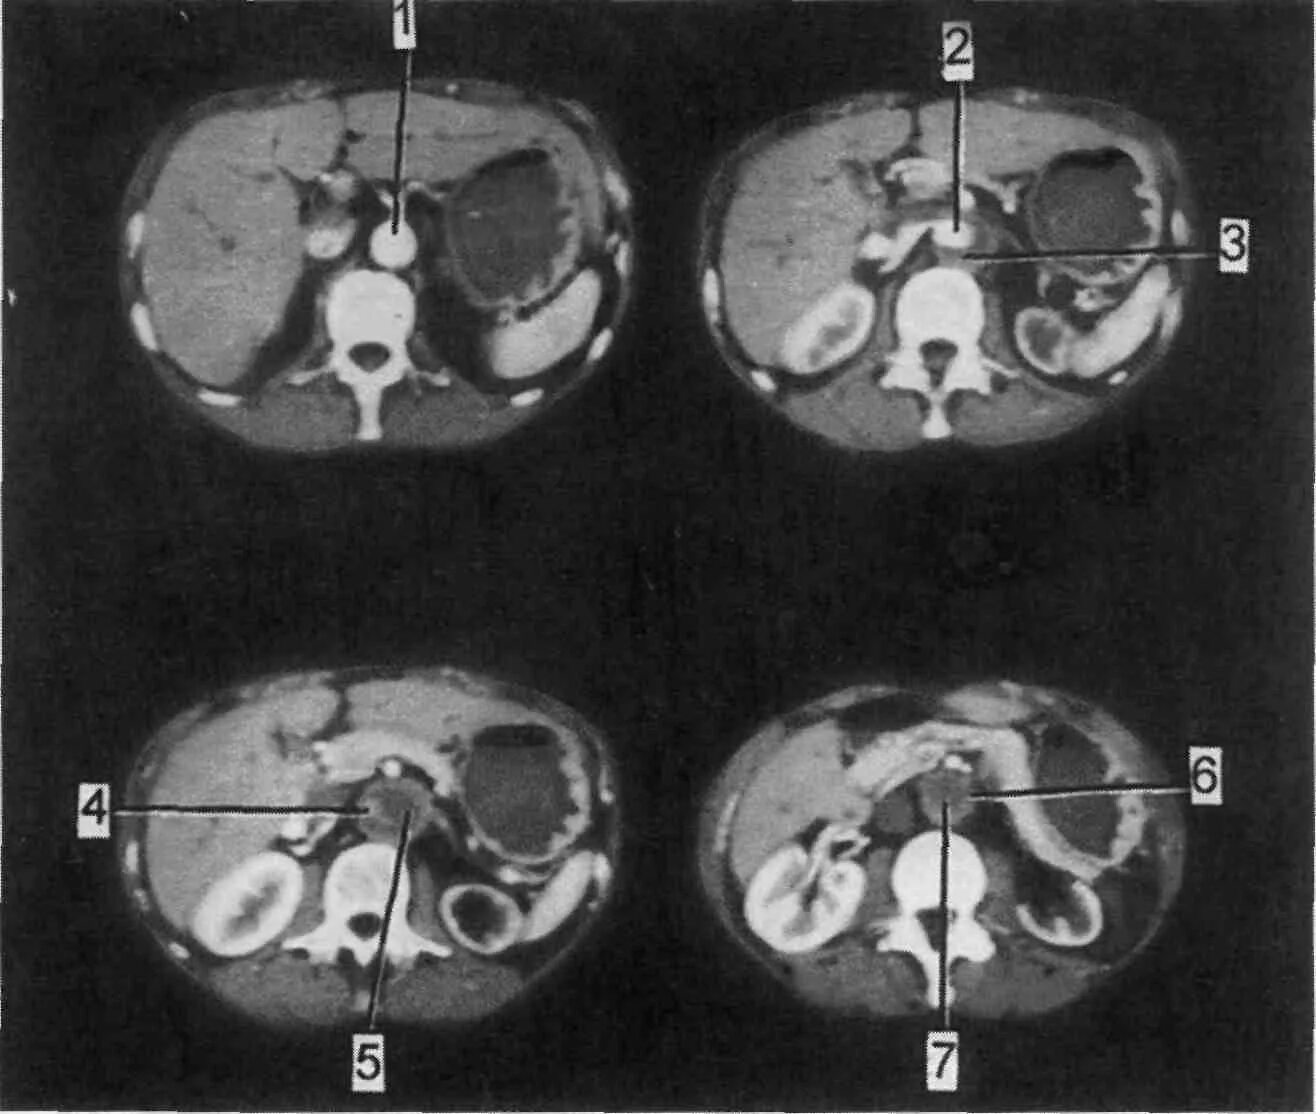

Тромбоз аневризмы аорты